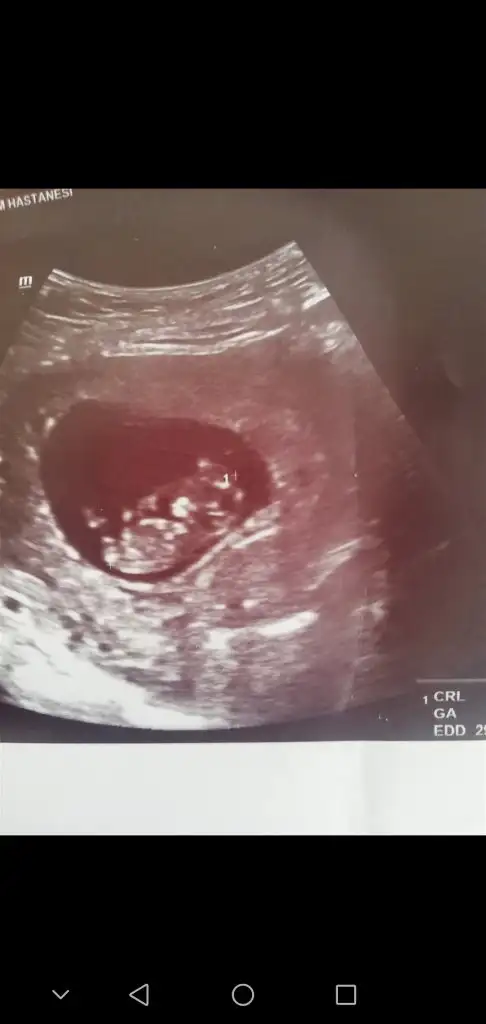

Ikra meyra Ikra meyra canim gecen sene kizimi tahminde dogru bilmistin 13+3haftalik tekrar gebeyim bi tahminde bulunurmusun bugun gittim devlette 16.haftaya kadar yasal olmadigi icin demiyorlarya dr al sen bak dedi verdi güldu🙃

Yaaa maşallah 🧿 kız gibi sanki emin olamadım